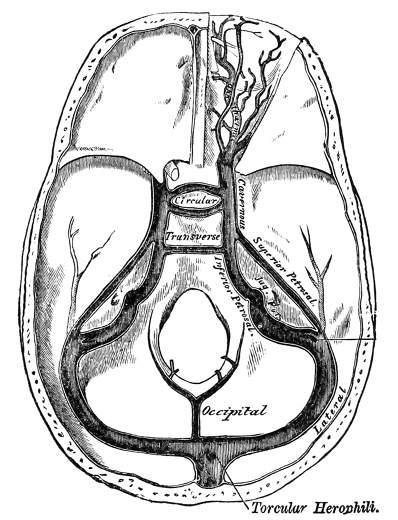

Fig. 3—Lymphatics of the head and neck.

B, the thoracic duct.